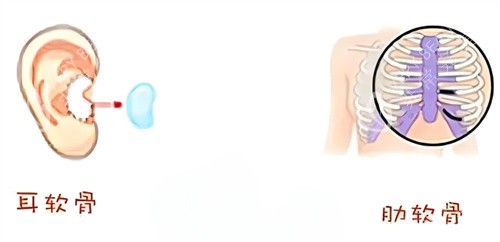

当时,医生跟我介绍说,用自己的肋骨隆鼻,材料取自自身,不会有排异反应,结果也会很自然。我心动不已,毫不犹豫地就做了手术。

我赶紧去医院询问医生,医生告诉我,这是肋骨鼻吸收的正常现象。原来,肋骨在植入鼻子后,会有一定程度的吸收,每个人的吸收情况不同,我的吸收情况相对明显一些。

假体隆鼻使用的是硅胶或者膨体等材料,它们的稳定性比较好,不会像肋骨那样出现吸收的情况。